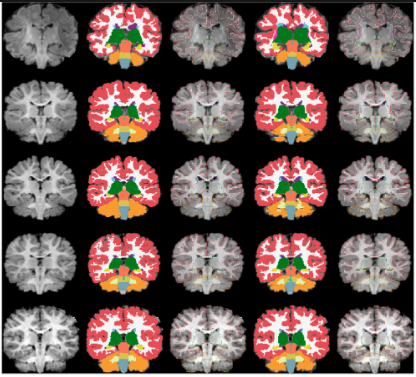

volumetric segmentation 과정 - GM/WM 분리한 데이터셋

참고 : 5가지로 segment한 부분은 Freesurfer colortable과 똑같은 색깔을 가지고 있다.

위 ↔ 아래 : 신생아/8개월/12개월/16개월/18개월

왼 ↔ 오른쪽 : 정규화 및 skullstripped T1 input 이미지 / 수동 segment / 바깥라인 수동 segment / 자동 segment / 바깥쪽 자동 segment

앞에 skull stripping한 T1 image를 가지고 와서 GW/WM로 구분하여 시각화함. 이때 5개의 부분을 나누어 segment하였음